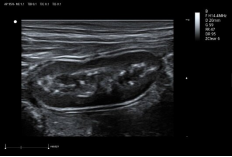

8L4PF ● 4.2-16.0MHz ● High-frequency linear array probe ● For Abdomen and Small Parts |

![]() |